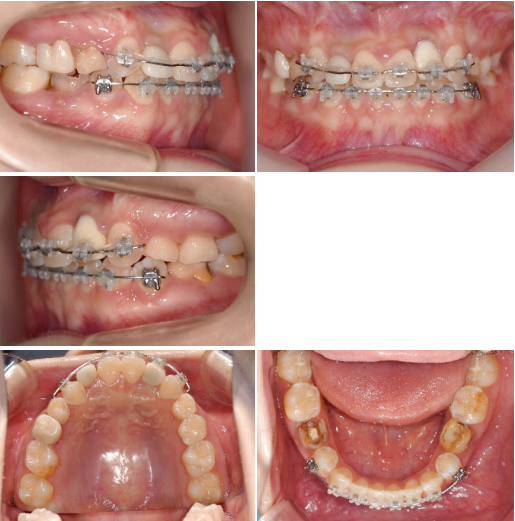

이 환자는 19세 여환으로 multiple congenitalmissing을 가지고 있으나 전치부 반대교합과 spacing의 해결만을 위해 내원하였습니다. 부분교정 시행후 상악 양측측절치 부위를 임플란트로 식립하기로결정하였습니다.

상악 양측 견치의 수직적 위치가 다른 것을 알 수 있습니다. 이는 추후 교정치료가마무리되면 전치부 교합평면의 canting이 확연히 보이게 되므로 문제가 될 수 있습니다.

반대교합 수정과 측절치 임플란트 식립및 temporary crown을 이용한 보철수복이 이루어졌습니다. 양측 견치의 수직적 차이가 조금 더 명확해졌습니다.

Occlusal canting을 수정하기 위해 상악 좌측 임플란트보철물에 bracket을 기울여 붙여서 slot의 방향대로 archwire가 삽입되었을때 좌측 견치는 정출되고 우측 견치는 함입되도록 하였습니다.

Slot의 방향에 맞춰 전치부 occlusalcanting이 개선되었습니다. 좌측견치의 정출이확연히 눈에 띕니다.

교정 마무리후 임플란트 상부 보철은 임시보철에서 최종보철로 변경해 주었습니다.

초진시부터 마무리까지 양측 견치 tip을 연결한 선을 기준으로 frontal occlusalplane의 변화를 비교 시occlusal canting의 개선을 확인할 수 있습니다.